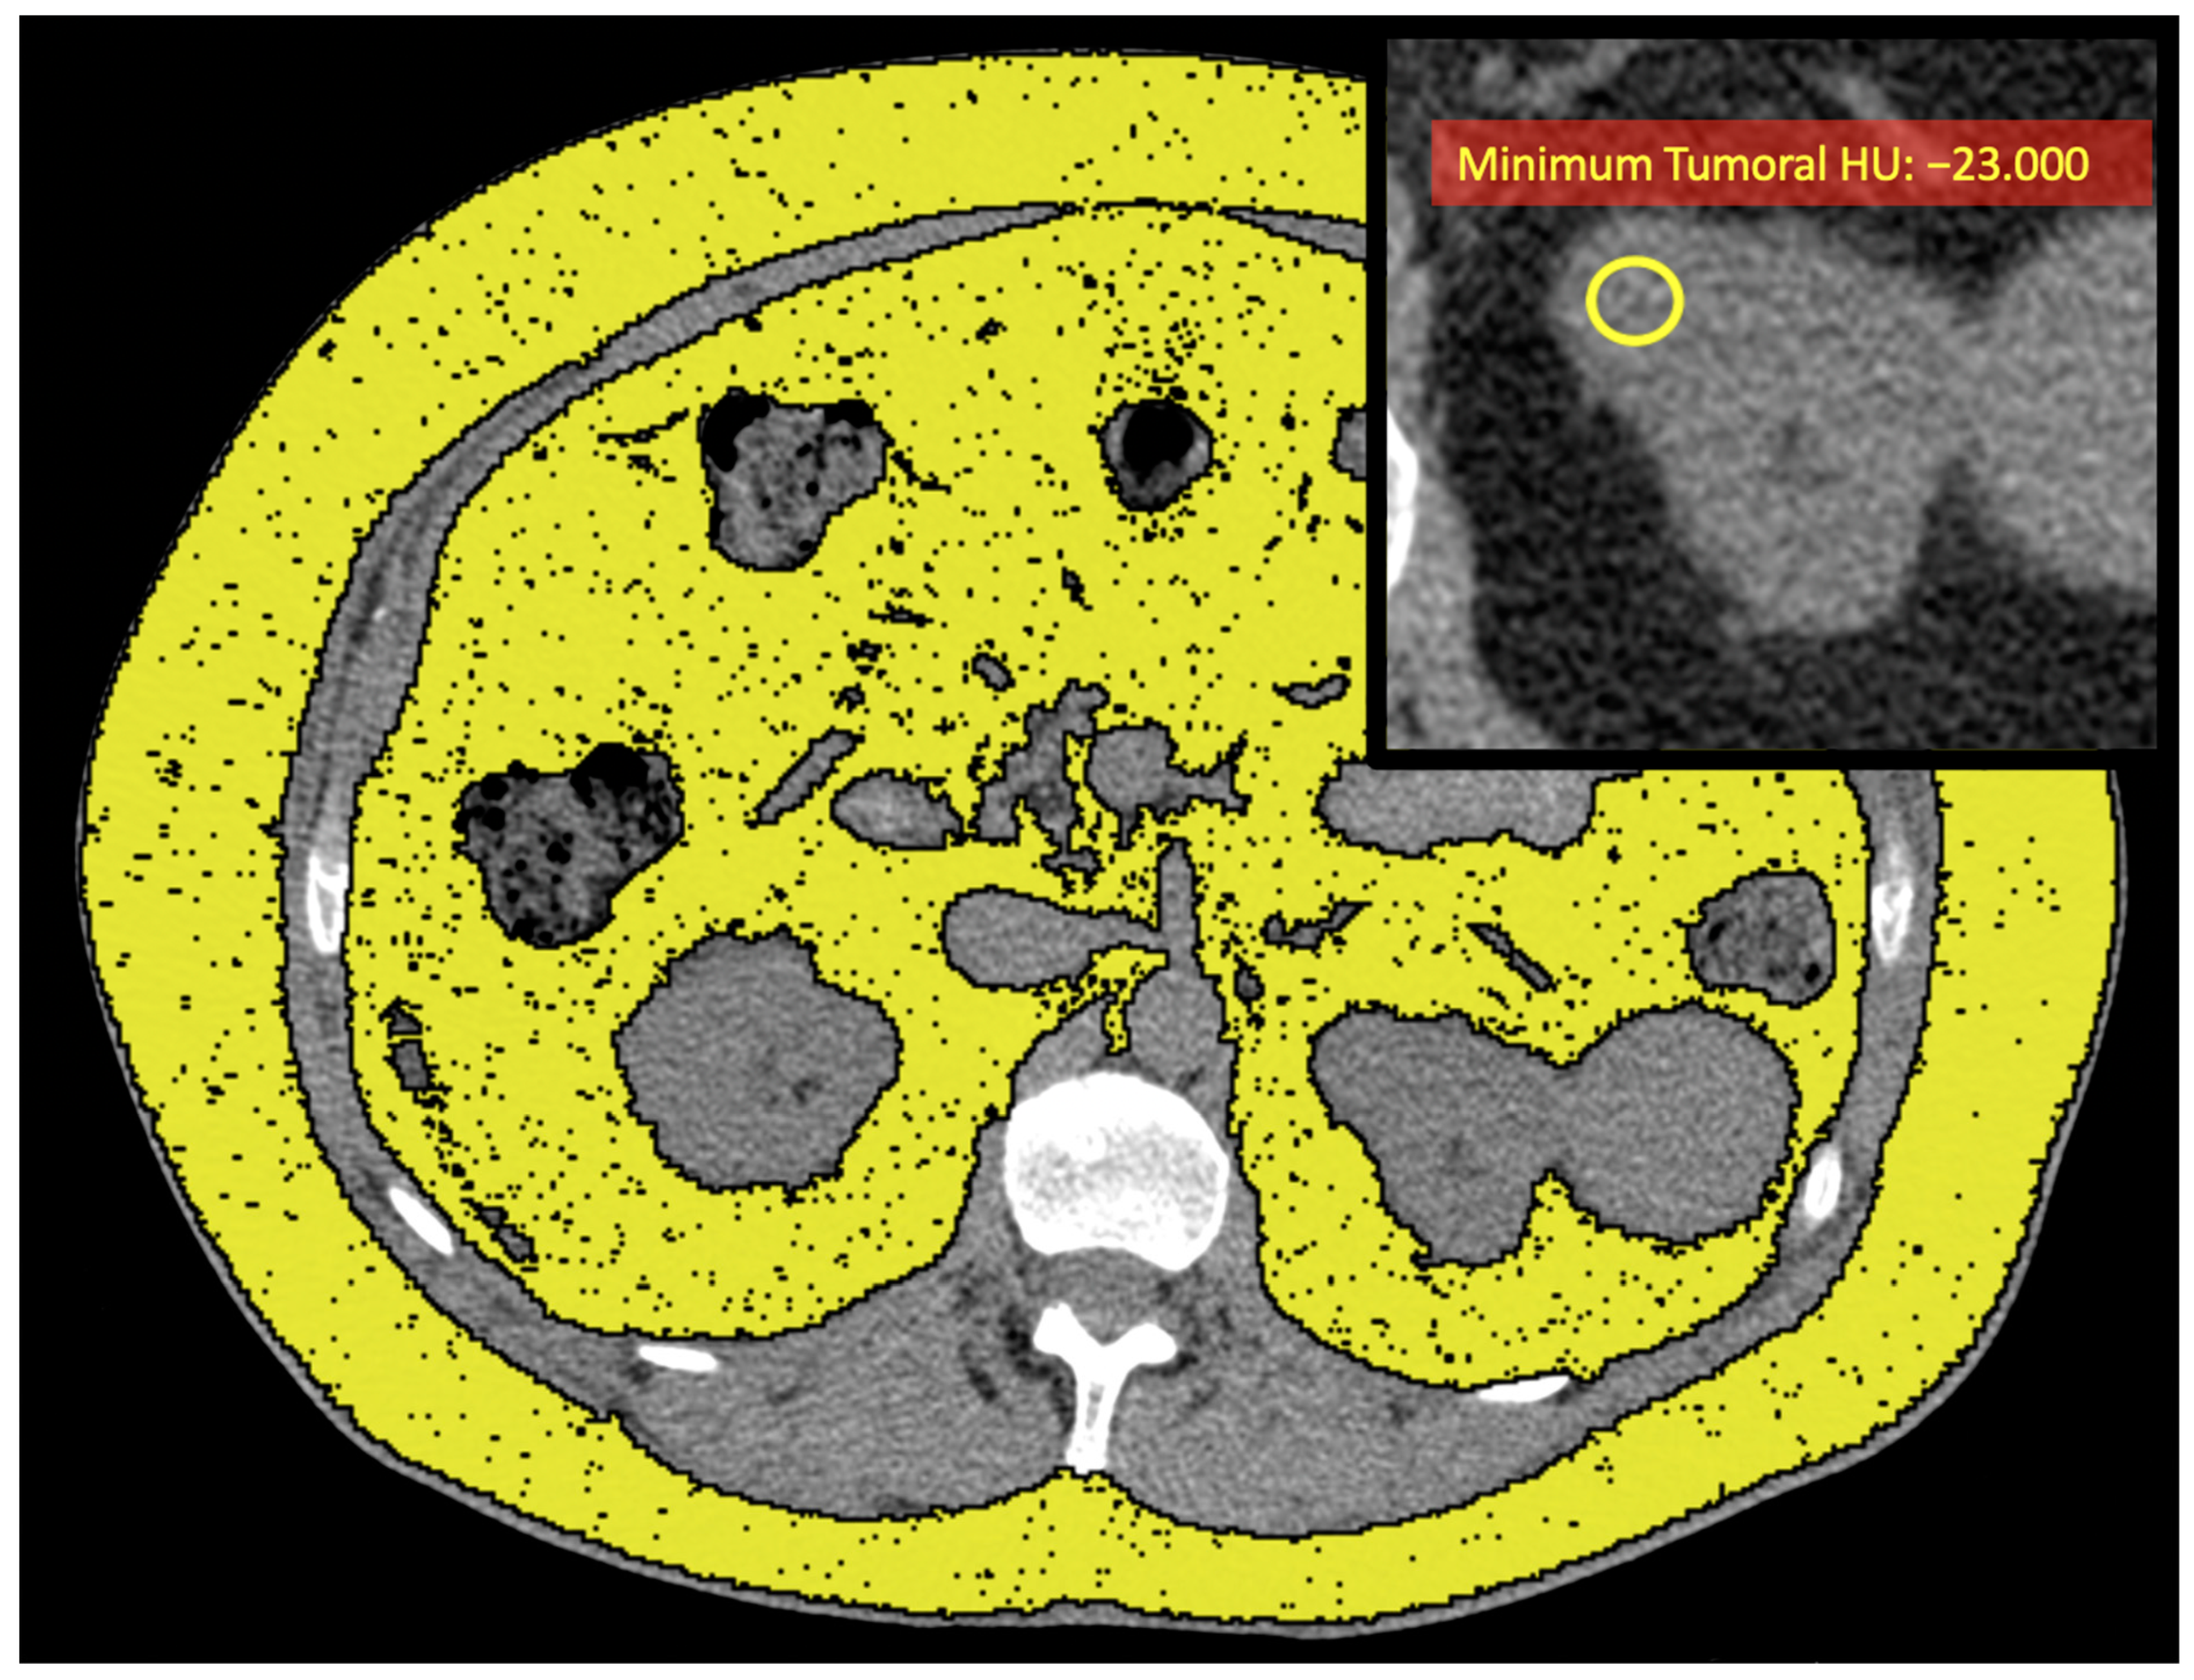

| Tumoral HUs | |||

| Median | 32 (27, 37) | 30 (24, 32) | 0.10 |

| Minimum | −6 (−16, 3) | −23 (−38, −13) | 0.006 |

| Maximum | 74 (62, 87) | 71 (63, 100) | 0.5 |